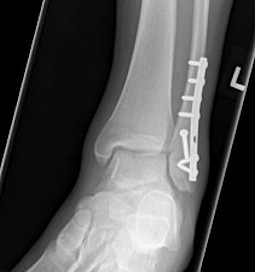

![]() |

Lateral talar shift / increased medial clear space / deltoid ligament injury

Tibia / fibular overlap < 1mm / syndesmotic injury